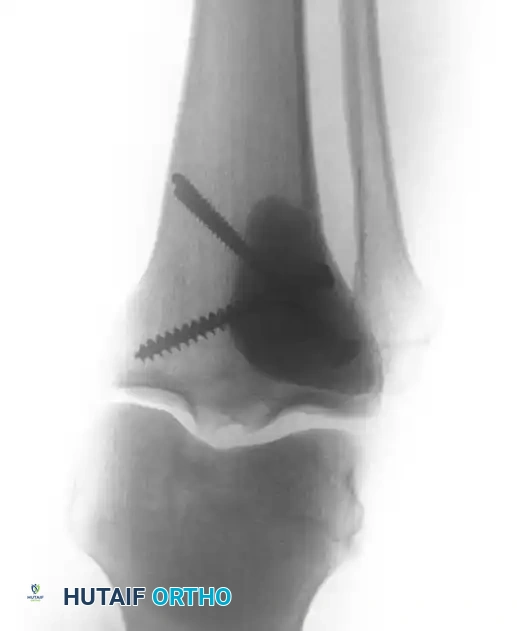

Following extended curettage, the structural integrity of the bone is compromised. The defect is typically reconstructed using PMMA cement, often augmented with internal fixation (screws or plates) to prevent pathological fracture.

Intraoperative view of a curetted cavity packed with PMMA cement and augmented with structural screws.

Postoperative radiographs demonstrating successful extended curettage, cementation, and screw augmentation of a distal tibial lesion.